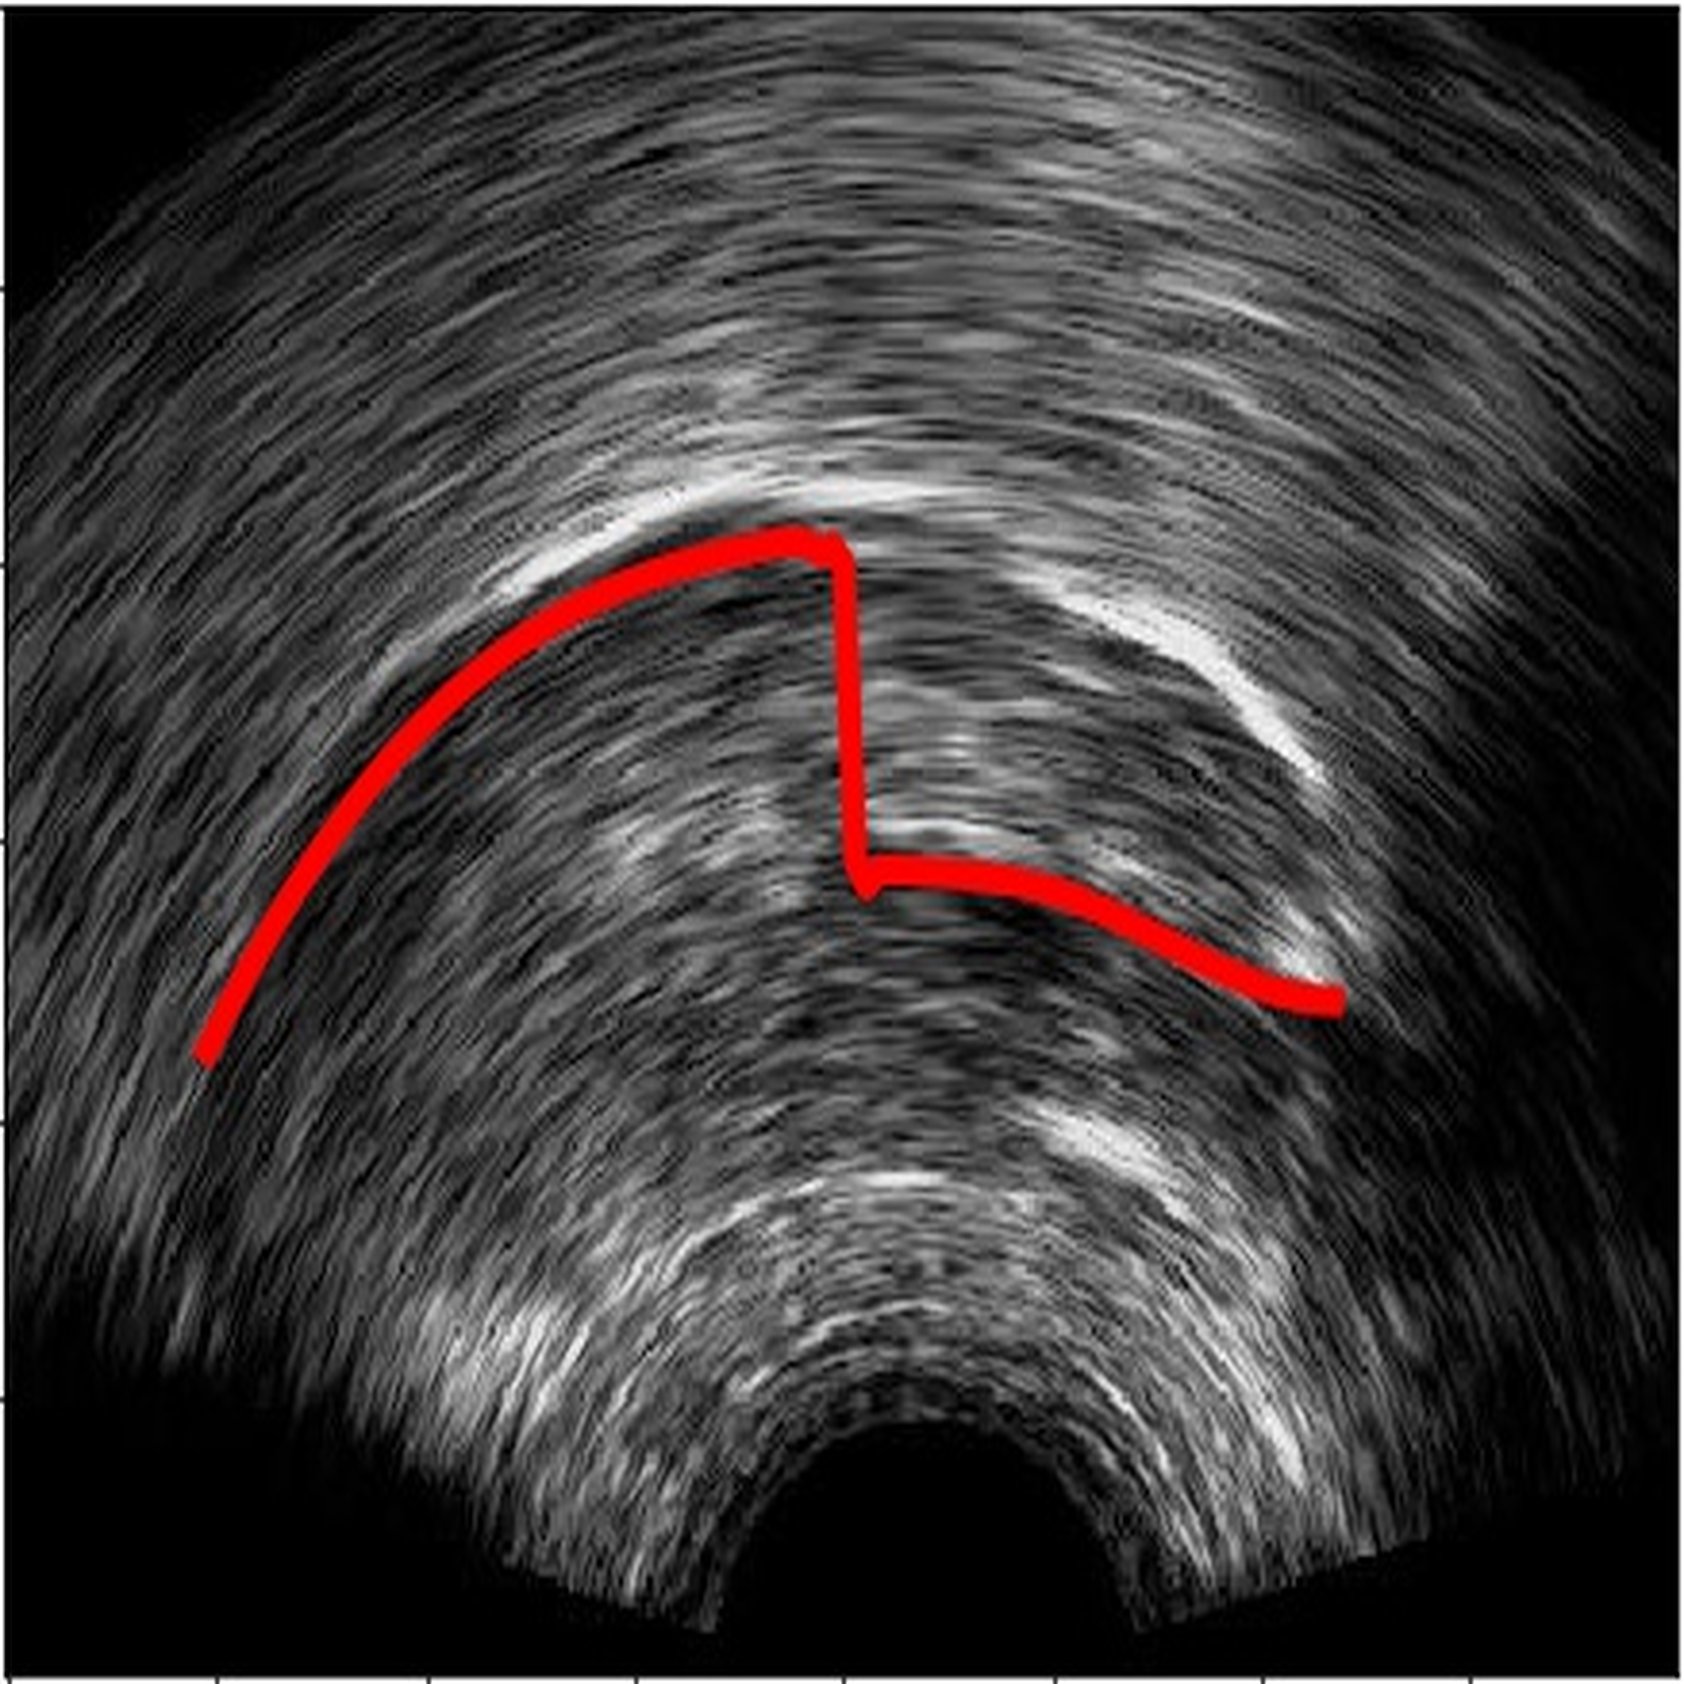

6 Error analysis

As the CNN is trained to identify the white edges directly corresponding to the tongue surface, additional or missing white edges due to bad image quality or speaker physiology can lead to failures in identifying parts of the tongue surface. In the absence of prior knowledge of plausible tongue shapes, the model will sometimes generate tracking errors when the white edge becomes blurry or interrupted. Similarly, bright edges in the image background are likely to be recognized as part of the tongue; tongue contours generated from image frames with these edges will likely suffer from implausible curvatures as interpolation in post-processing attempts to connect these regions. There some potential solutions to these problems, including incorporating temporal constraints on tongue contour variations across frames [3], or adding a smooth constraints that penalizes discontinuity of tongue contours, or introducing a strong prior probability of possible tongue locations. In data processing, these issues can also be mitigated by tuning the parameters in post-processing to match the needs of the specific dataset, and remaining errors can also be addressed through manual correction (as even then, the workload is considerably reduced relative to manually labeling all frames).